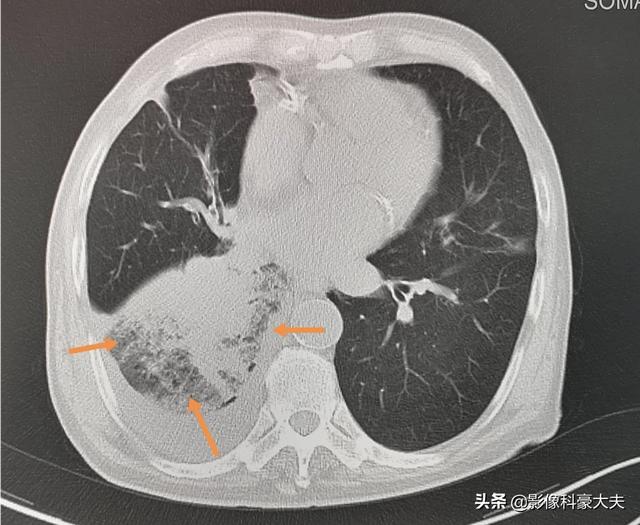

Il s'agit d'un homme de 79 ans atteint d'un cancer du poumon à petites cellules depuis 4 ans, en raison du rétrécissement de la bronche du lobe inférieur droit, provoquant une pneumonie obstructive et une forte fièvre récurrente, un état qui peut également être fatal si l'infection n'est pas contrôlée, et le vieil homme est en bonne santé actuellement.